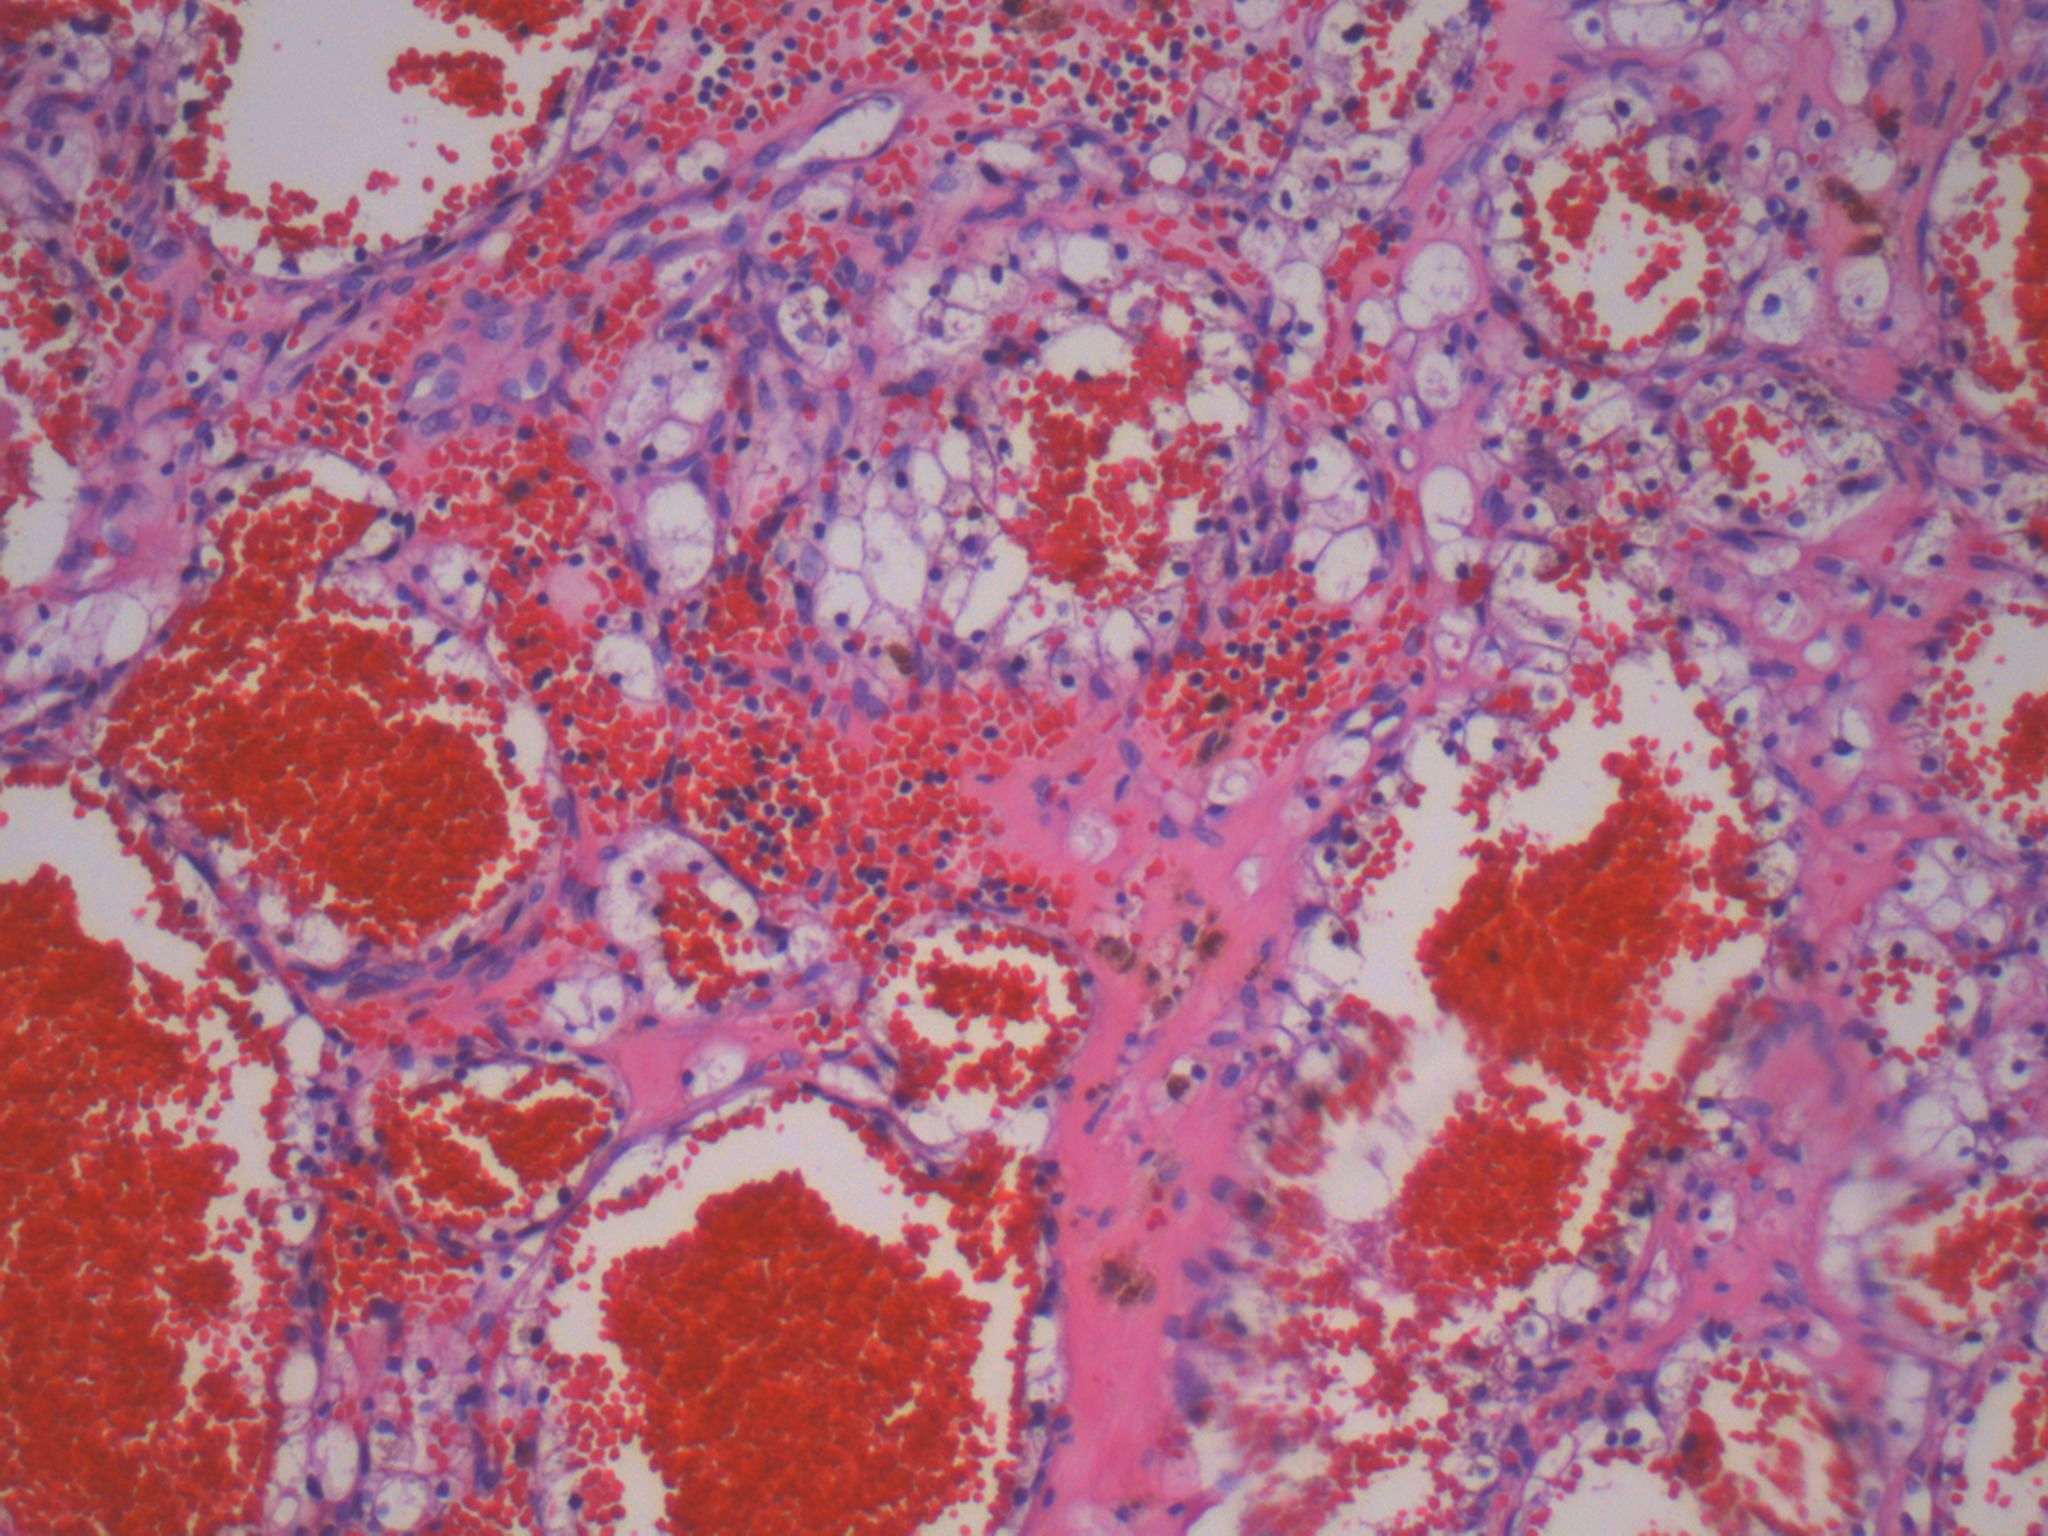

Consensus grade: Clear cell RCC

clear cell RCC with cystic changes

Cystic tumour with clear cells.